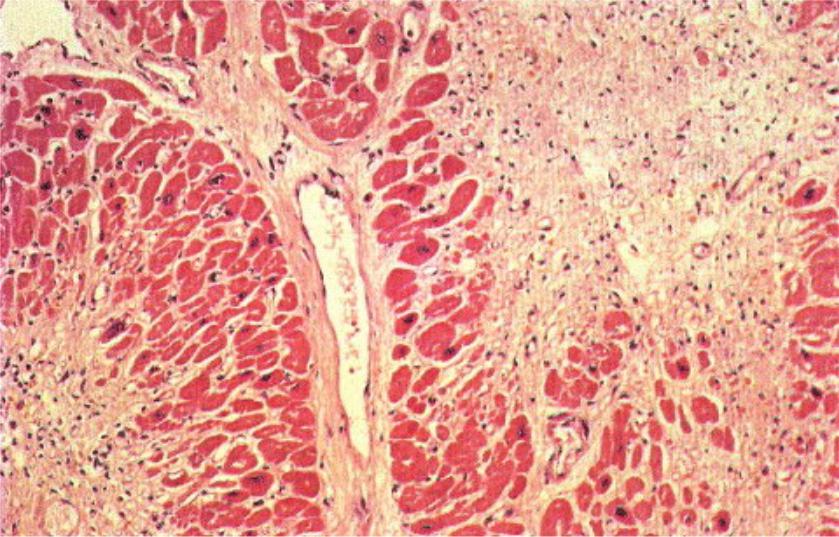

Межуточный миокардит: гистологические исследования